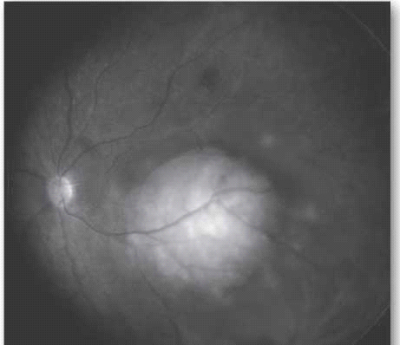

בבדיקת עיניים יתגלה נגע מורם בגוון קרמי או צהוב חיוור, המלווה בנוזל תת-רשתי[23] (תמונה 5), בקוטר מקסימלי ממוצע של 9 מילימטר ובעובי ממוצע של 3 מילימטר[26]. בכשליש מהמקרים יופיעו מספר מוקדים גרורתיים בעין[16]. יש לציין כי יש גידולים השולחים גרורות בעלות מראה ייחודי ואופייני; למשל קרצינומה של בלוטת התריס וקרצינואיד נוטים לשלוח גרורות בעלות גוון כתום אופייני.